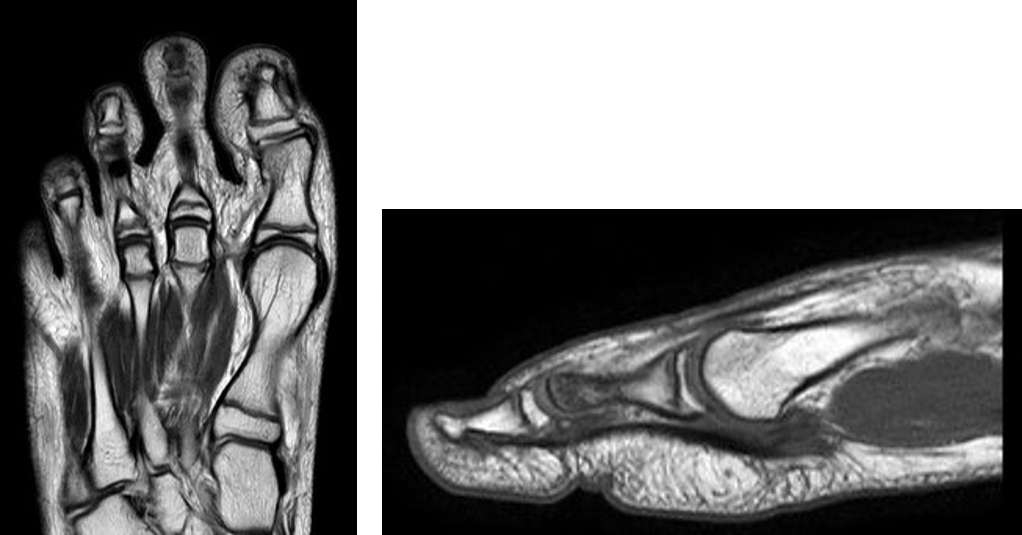

整形領域の撮影

当センターでは、体幹部のみならず四肢の撮影も行っております。膝関節、肩関節、手関節、足関節など整形領域の撮影も行っております。最新のAI技術を用いることで、より細かく描出できるようになり、靭帯損傷や骨折、筋損傷を見つけることが出来ます。

『手関節MRI画像』

『足部MRI画像』